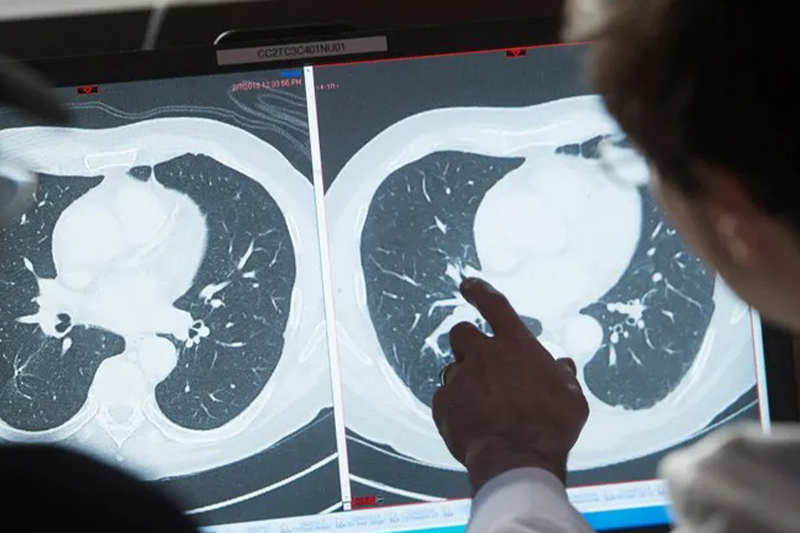

أكدت الشبكة المغربية للدفاع عن الحق في الصحة والحق في الحياة، أنه رغم كل المجهودات المبذولة بالمغرب في مجال الوقاية وعلاج السرطان، إلا أن المؤشرات الوبائية الخاصة بهذا المرض “تظل مقلقة”. وأوضحت الشبكة، في بلاغ لها بمناسبة اليوم العالمي لمكافحة السرطان (4 فبراير) الذي اختارت منظمة الصحة العالمية تخليده هذه السنة تحت شعار “سد فجوة […]readmore

أكد البروفسور عبد اللطيف بنيدر، أخصائي في علاج الأورام والمدير السابق لمركز محمد السادس لعلاج السرطان، أن المغرب يبذل جهودا كبيرة في الوقاية والتشخيص المبكر للسرطان ، وذلك من خلال على الخصوص، المخططين الوطنيين للوقاية ومراقبة السرطان، وكذا الوعي بأهمية التشخيص المبكر للسرطان من خلال إجراء فحص فيروس الورم الحليمي البشري المسؤول عن سرطان عنق […]readmore